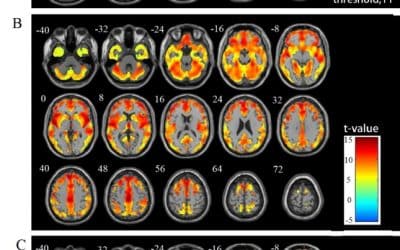

Changes in whole-brain functional networks and memory performance in aging

Abstract We used resting-functional magnetic resonance imaging data from 98 healthy older adults to analyze how local and global measures of functional brain connectivity are affected by age, and whether they are related to differences in memory performance....